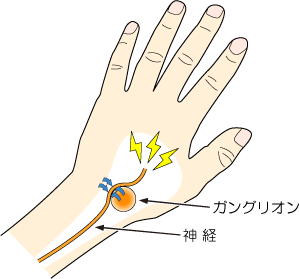

腫瘍:ガングリオン

▶ 症状

手首の甲、手首の内側、手掌部などにグリグリとした膨らみができます。出現時痛みが生じますが、改善します。手首の甲にできると神経を圧迫することがあり、手をつくときに痛みがあります。

▶ 特徴、原因

手に発生する腫瘍の中で最も多く、若年成人に多く、約3:1の割合で女性に多いです。関節の靱帯や腱鞘の粘液変性が誘因となって発生すると考えられています。

▶ 治療

痛みがなく、整容的にも問題ない場合、放置しておいても構いません。穿刺、吸引することもありますが、再発率が高いです。再発を繰り返す場合、手術治療をお勧めします。基本的に日帰り手術が可能です。